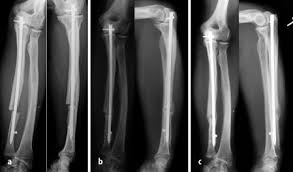

Pdf Rekonstruktion Nach Unterschenkelfehlheilung